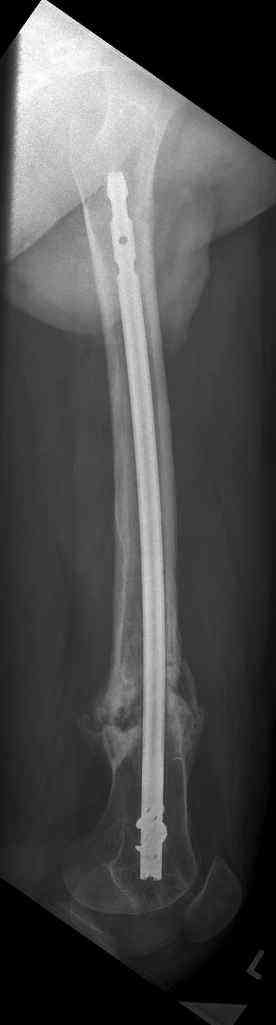

16 yr old boy, high energy motorcycle trauma trauma in July 2005 with:

- hip dislocation + acetabular fracture L

- distal femoral fracture L

- tibial shaft fracture L

- metatarsal fractures L

july 05: LISS femur, LCP plate tibia, double recon. plate post. acetabulum

oct 05: cancellous bone graft femur

aug 06: blade plate + bone graft

nov 06: revision blade plate

feb 07: retrograde nail + bone graft + BMP

may 07: dynamisation nail

sept 07: locking screw removal (max. dynamisation reached)

nov 07: persistant non-union distal femur; other fractures healed uneventfully.